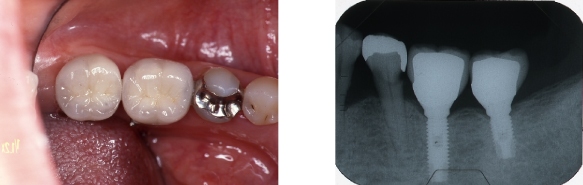

インプラント症例③ ~ほとんど歯が無い例~

●残っている歯が2本しかなく、上下、入れ歯を何度と作っているが、全然合わない。

●上にはインプラントを6本入れて、固定式の歯を入れました。

●下にはインプラントを4本入れて、マグネットを取り付けて、安定する入れ歯にしました。

※インプラントにするには、支えとなる骨が必要です。

場合によっては、事前に骨を作る処置を行います。